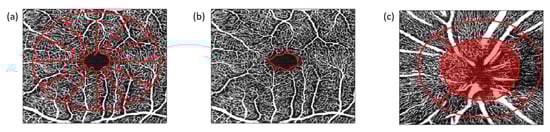

4.3. OCT–Angiography (OCT–A)